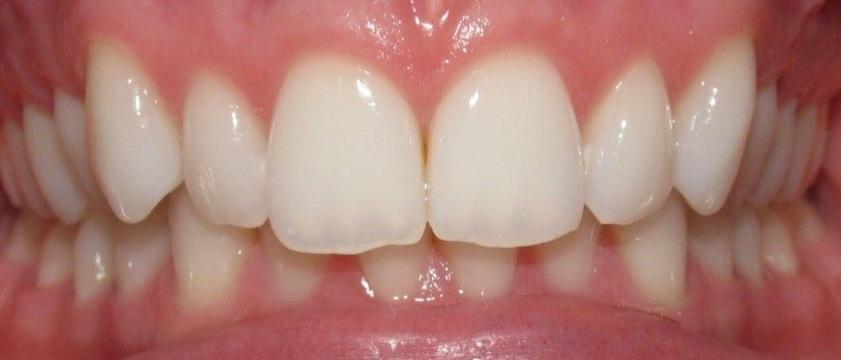

Overbite occurs when the lower and upper jaws and/or teeth are not aligned, causing the upper front teeth to cover the lower front teeth. Most often an overbite is hereditary, but it can also be caused by the jaw not forming correctly.